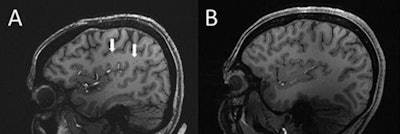

Xu's group used ultrahigh field 7T MRI to compare structural microvascular changes in people with different types of migraines and compared them to migraine-free controls. The team used data from 10 patients with chronic migraines, 10 with episodic migraines without aura, and five who were free of migraines.

They found that the number of enlarged perivascular spaces in the centrum semiovale was significantly higher with migraines compared to healthy controls (p = 0.04). The researchers also found that the frequency of white matter hyperintensities and cerebral microbleeds did not differ significantly between the migraine sufferers and the healthy control group. However, migraine patients showed a significant correlation between enlarged perivascular space in the centrum semiovale and the severity of deep white matter hyperintensities (p = 0.04).